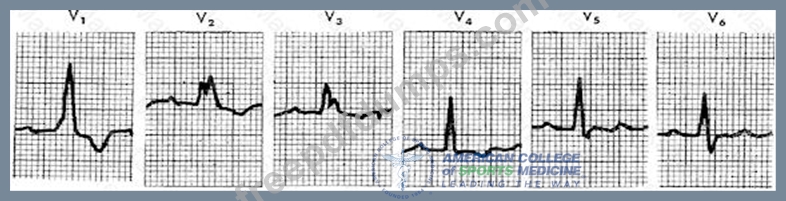

In the ECG strip shown below, what abnormality is indicated?